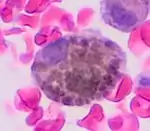

Cytology of a macrophage with typical features. Wright stain. | |